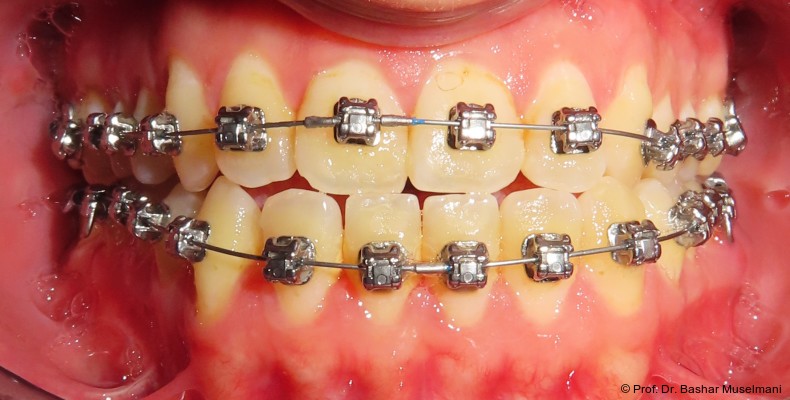

Bogensequenz und mechanische Umsetzung

Der Bogenwechsel erfolgte in einem standardisierten Intervall von acht Wochen. Die Sequenz war in beiden Kiefern weitgehend identisch und wie folgt aufgebaut:

• 0.013" CuNiTi (OK / UK)

• 0.016" CuNiTi (OK / UK)

• 0.018" CuNiTi (OK / UK)

• 0.014 x 0.0275" CuNiTi (OK / UK)

• 0.016 x 0.0275" Edelstahl (OK)

• 0.018 x 0.0275" CuNiTi (OK / UK)

• Abschlussbogen: 0.018 x 0.0275" TMA (OK/UK)

Diese Sequenz ermöglichte eine schrittweise Ausformung der Zahnbögen, eine kontrollierte Torque-Expression sowie eine präzise Feineinstellung in der Abschlussphase (Abb. 5a–e).

Zwischenbefund

Während des Behandlungsverlaufs wurden ein Kontroll-Fernröntgenseitenbild sowie ein Orthopantomogramm angefertigt.

Fernröntgenologische Befunde (Zwischenkontrolle)

• SNA: 81,9°

• SNB: 83,9°

• ANB: −2,1°

• Wits-Wert: −2,0 mm

Es zeigte sich eine deutliche Verbesserung der sagittalen Relation bei unveränderter skelettaler Basis, was die Effektivität der dentoalveolären Kompensation unterstreich.